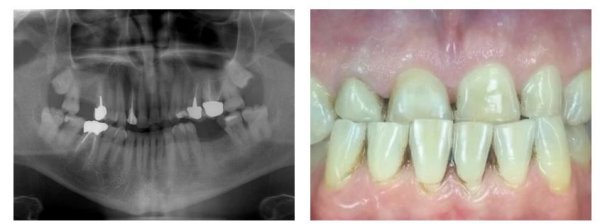

Tooth number 46 had a root canal treatment that was restored with a full gold crown. The patient presented with a fistula in the buccal furcation region. Upon probing, depth was greater than 10mm and a PA of the area showed a lesion from the apical third of the mesial root up to the furcation. Clinical and radiographic findings were consistent with a root fracture.